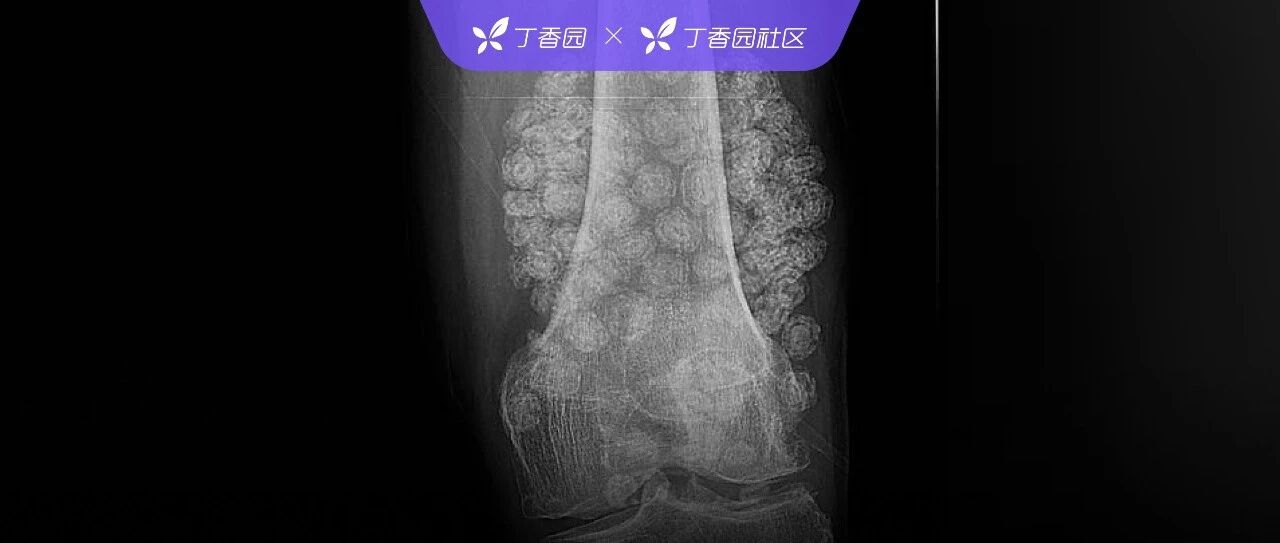

关节里长满「珍珠」?家属慌了!接诊医生却一眼秒杀:这病 6 年前就改名了! 丁香园 · 公众号 · 医学 · 昨天 · |